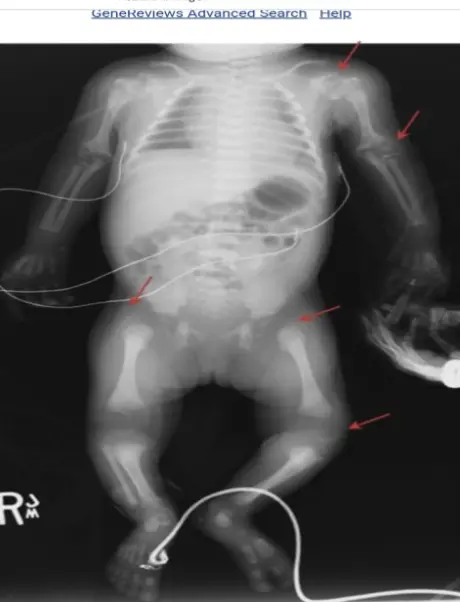

- Radiographic: Stippling of epiphyses (Chondrodysplasia punctata).

Diagnosis

Is made when the following are both present::

- The mother has anti-Ro, anti-La, or anti-ribonucleoprotein (RNP) antibodies.

- The fetus or newborn develops HB, or the newborn develops the typical rash or hepatic or hematologic manifestations in the absence of another explanation